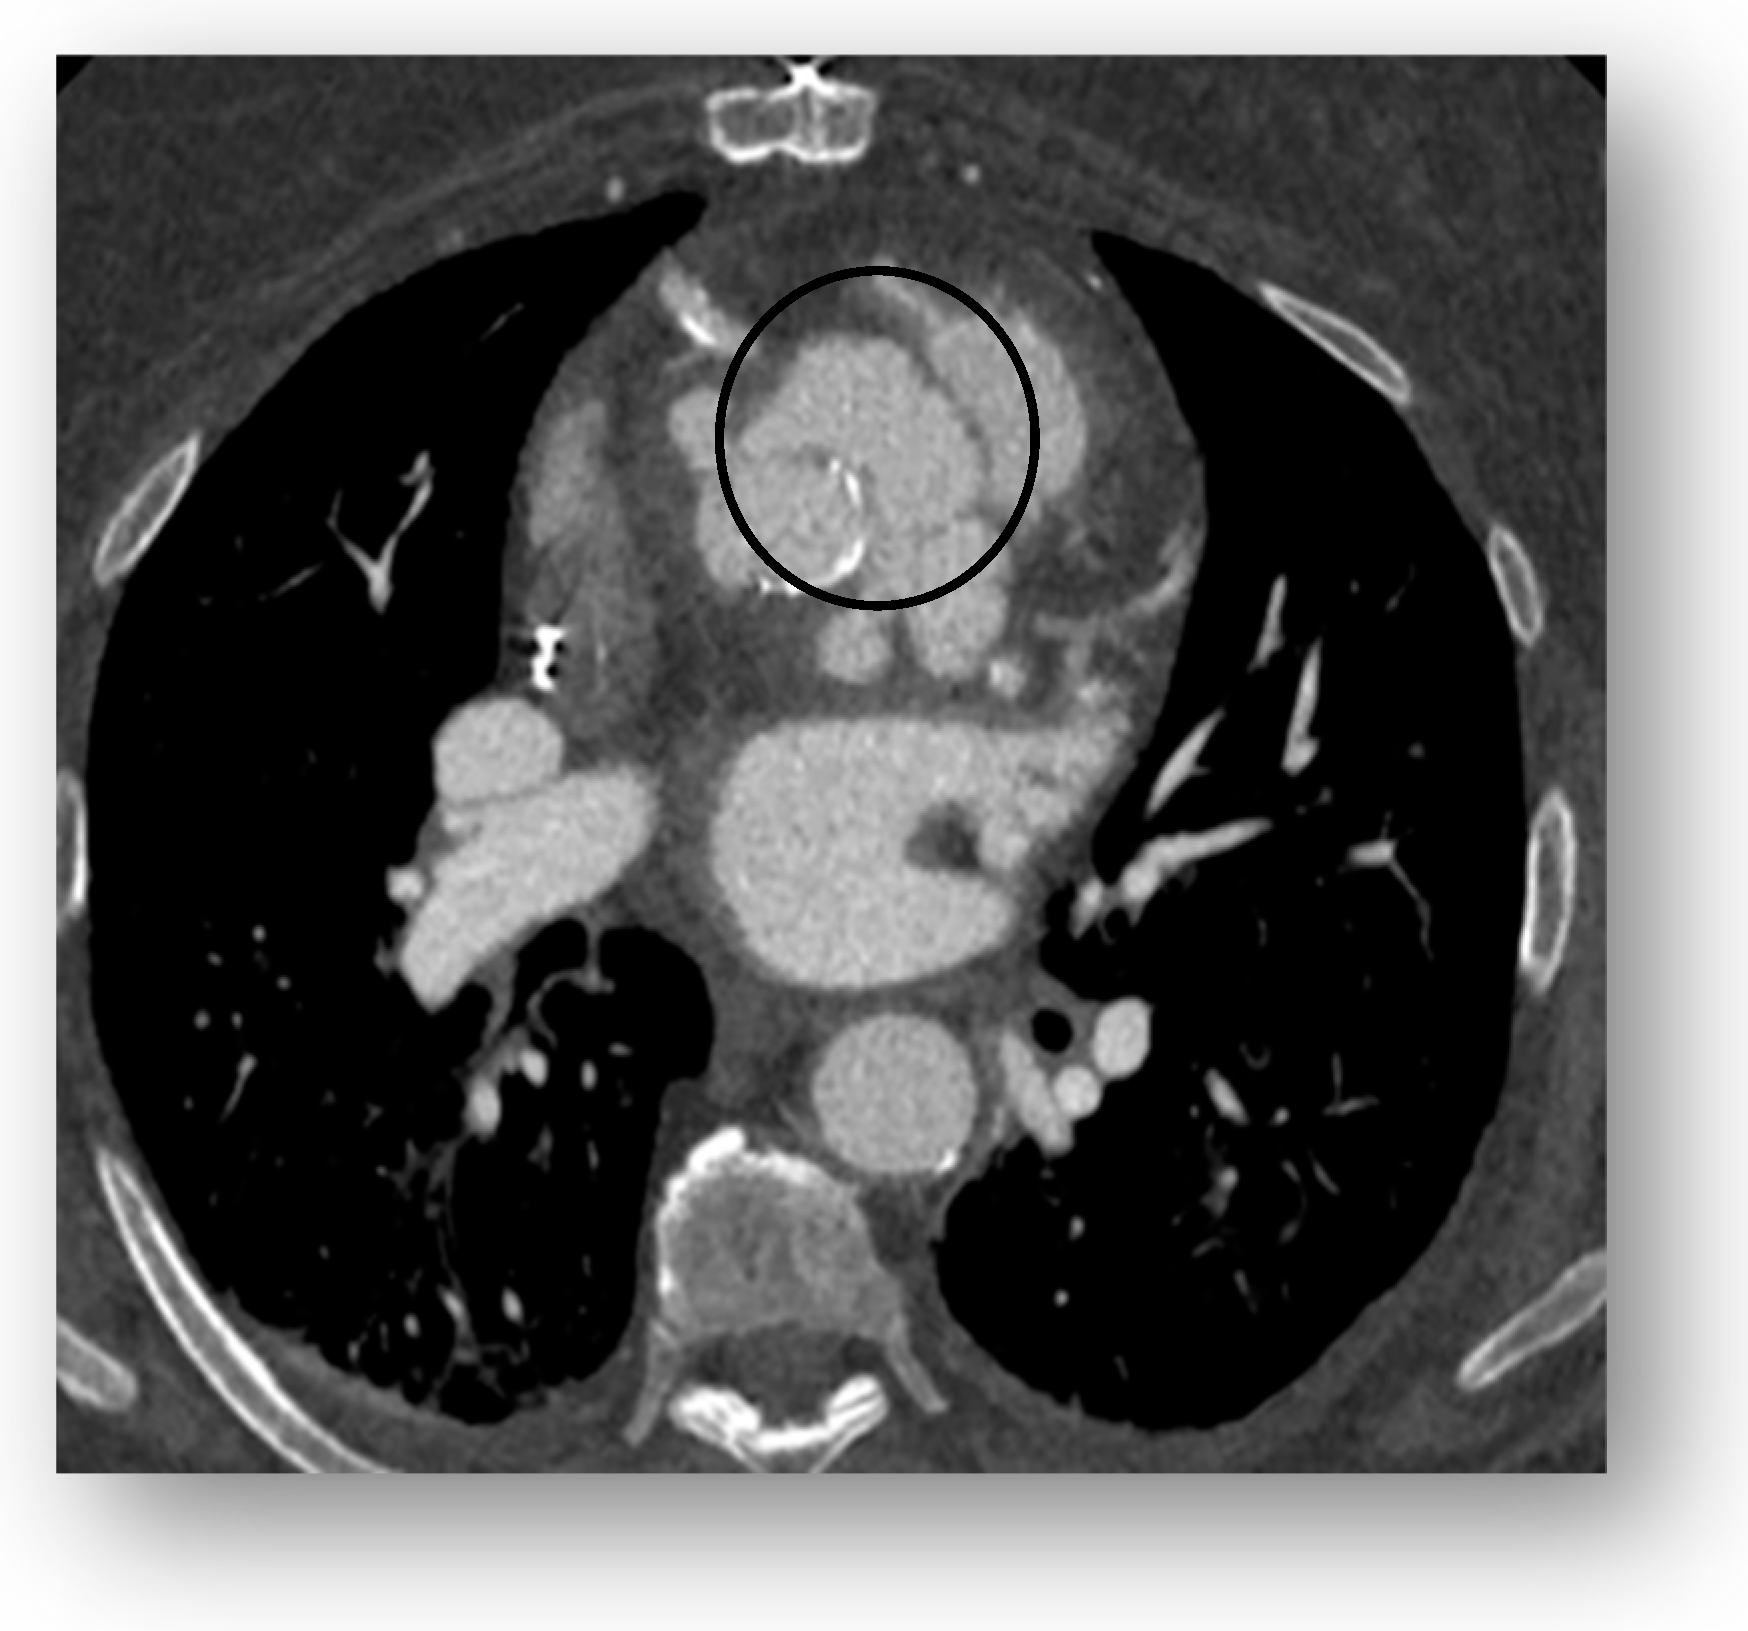

5. Cardiac Computed Tomography

- Cardiac CT: While excellent for anatomical definition, cardiac CT has limited sensitivity for small (<10 mm) mobile vegetations and cannot assess hemodynamic status. Its use is also limited by radiation exposure and the need for a stable sinus rhythm for accurate electrocardiographic gating, as arrhythmias can degrade image resolution and diagnostic yield [37,60,61]. Additionally, the use of iodinated contrast media carries a risk of nephrotoxicity, a relevant concern in a patient population often affected by chronic kidney disease.